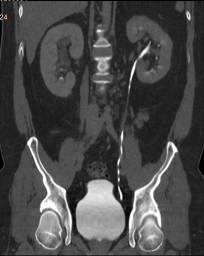

Chẩn đoán hình ảnh mô mềm tiên tiến cho vùng bụng.

Tăng cường độ tương phản I-ốt.

Hỗ trợ đánh giá an toàn cho bệnh nhân.

Đảm bảo hình ảnh chất lượng cao.